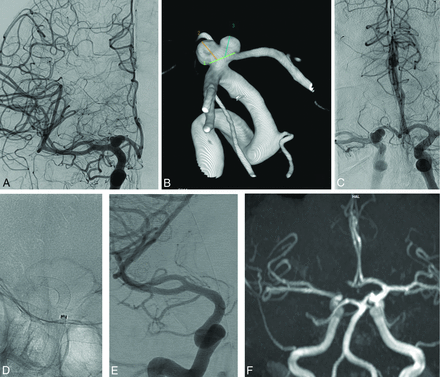

Patient 4. A, A right ICA angiogram (anterior-posterior view) shows a wide-neck medium-sized ICA terminus aneurysm. B, 3D reconstruction depicts a bilobate irregular shape of the aneurysm with the right A1 segment originating from the neck. C, Contralateral ICA angiogram demonstrates the patency of the AcomA with retrograde flow into the left ICA terminus segment. D, A 4.5 × 14 mm PED is deployed from the M1 (before the temporal branch) to the supraclinoid ICA, avoiding, as much as possible, the ostium of the ophthalmic artery. E, After 12 months, the aneurysm is completely occluded, and the right A1 shows absence of anterograde flow. The lateral lenticulostriate arteries and the temporal branch of the MCA are patent. F, The time-of-flight 3D reconstruction sequence shows absence of flow into the aneurysm (OKM D occlusion) and retrograde filling of the right anterior cerebral artery from the contralateral side through the AcomA.